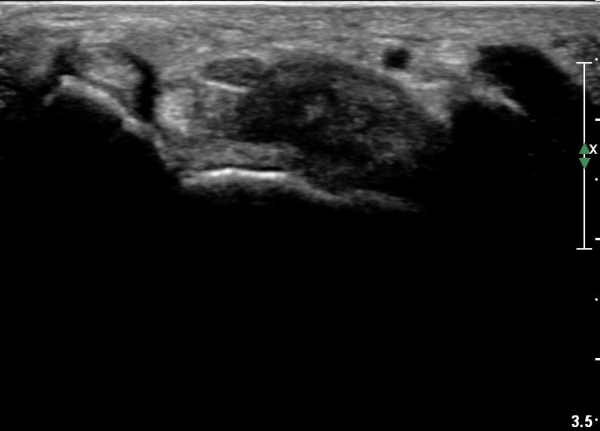

¼Õ¹Ù´Ú ±ÙÀ§ºÎ Ⱦ´Ü¸é°Ë»ç¿¡¼­ Á¤Á߽ŰæÀº ºÎÁ¾ µî ƯÀÌ ¼Ò°ßÀÌ º¸ÀÌÁö ¾ÊÀ¸³ª

¹«Áö±Ù °æ°èºÎ ̫̿¿¡ Àú¿¡ÄÚ Á¾¾çÀÌ °üÂûµÈ´Ù(»çÁø 4, 5).

¼Õ¹Ù´Ú ±ÙÀ§ºÎ¾Æ·¡·Î ŽÃËÀÚ¸¦ À̵¿ÇÏ´Ï Á¾¾çÀÌ ´õ Ä¿Áö°í Á¤Á߽ŰæÀÇ ¹«Áö±Ù °¡Áö°¡ °üÂûµÈ´Ù.(»çÁø 6).

ŽÃËÀÚ¸¦ Á¶±Ý ´õ ¸»´ÜÀ¸·Î À̵¿ÇÏ´Ï Á¾¾çÀÌ ´õ Ä¿Áö°í Á¤Á߽ŰæÀÇ ¹«Áö±Ù °¡ÁöÀÇ ¾Ð¹ÚÀÌ

°üÂûµÈ´Ù.(»çÁø 7, 8).